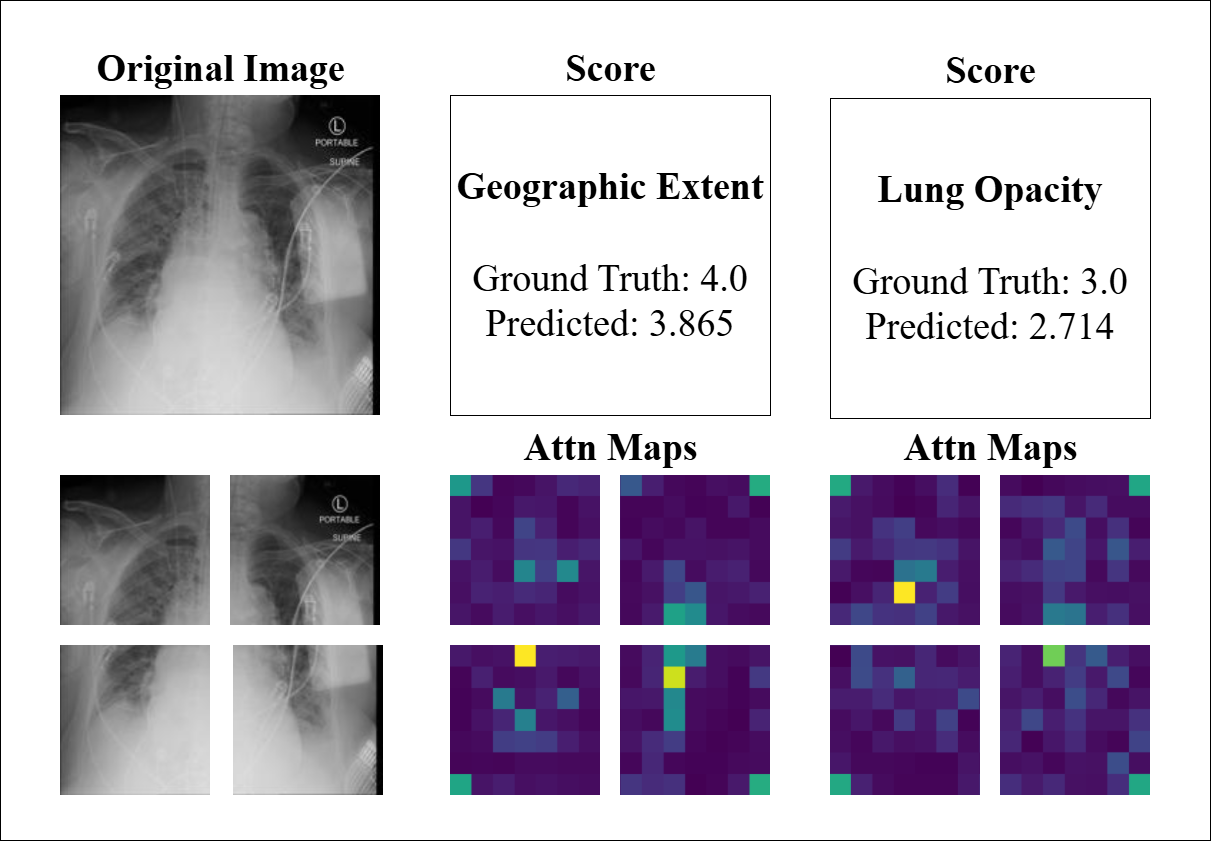

To further evaluate the interpretability and consistency of our model, we conducted a visual inspection of attention maps and prediction outcomes across representative CXR and CT cases. Figure 7 displays three CXR examples alongside their corresponding quadrant-wise attention maps that represent the output of the four PVT encoders, as well as the GT and predicted scores for both GE and LO. The attention maps demonstrate the model’s ability to localize clinically relevant radiographic features, with predictions largely consistent with GT scores (e.g., LO: GT 3.0 vs. predicted 2.714). Notably, the attention weights align with the predicted severity, as the model’s scores reflect the proportion of high-weight regions within the maps. However, the last example (GT 2.5 vs. predicted 5.86) exhibits a significant deviation. While the attention maps highlight diffuse areas of activation, the overestimation may arise from image-quality limitations, such as low contrast or anatomical noise, which could lead the model to misinterpret benign variations as pathological findings. This underscores the influence of technical artifacts on model performance and highlights the need for robust preprocessing to enhance reliability.